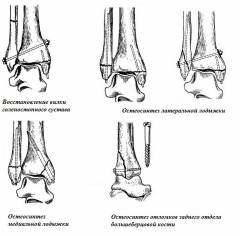

Виды операций при переломе лодыжек (рис. 10)

- Скрепление межберцового соединения (восстановление вилки) – болт закрепляют через малоберцовую и большеберцовую кости под углом от латеральной лодыжки, дополнительная фиксация с помощью гвоздя медиальной лодыжки.

Все каналы предварительно формируют сверлом.

Показания к операции: перелом малоберцовой кости и медиальной лодыжки (ротационные переломы), другие переломы с разрывом межберцового соединения.

- Остеосинтез латеральной лодыжки – через лодыжку вдоль оси малоберцовой кости вводят штифт, дополнительно гвоздем фиксируют штифтом медиальную лодыжку. При разрыве межберцового соединения – скрепляют его.

Показания к операции: пронационные переломы.

- Остеосинтез медиальной лодыжки – медиальную лодыжку фиксируют двухлопастным гвоздем под прямым углом к линии перелома. Дополнительно штифтом фиксируют и латеральную лодыжку. Возможны дополнительные прикрепления отломков винтами.

Показания к операции: супинационные переломы.

- Остеосинтез отломков большеберцовой кости – через вскрытый голеностопный сустав длинным шурупом соединяют отломки большеберцовой кости, иногда требуется дополнительный шуруп, который прикрепляют вдоль оси кости.

Показания к операции: перелом большеберцовой кости по заднему отделу дистального конца.

Рис. 10. Схематическое изображение основных видов операций при переломе лодыжек.